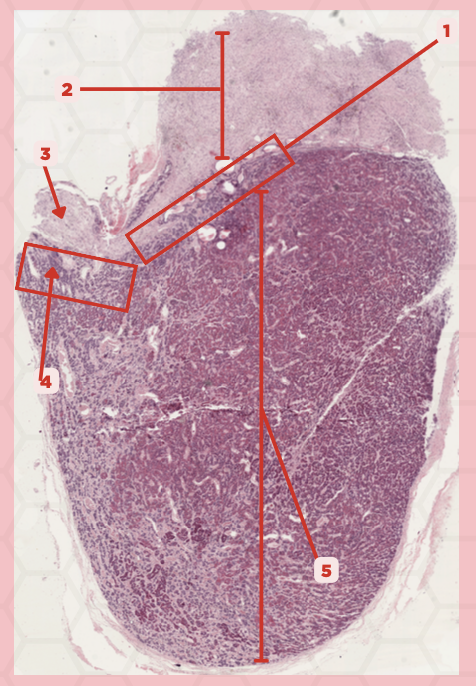

Pituitary

Identify the specimen.

Anterior Lobe

Identify the structure labeled as 1.

Posterior Lobe

Identify the structure labeled as 2.

Intermediate Lobe

Identify the structure labeled as 3.

Pars Tuberalis

Identify the structure labeled as 4.

Pituitary Stalk

Identify the structure labeled as 5.

Neural Ectoderm

What ectoderm is #2  derived from?

Oral Ectoderm

What ectoderm #1, #3, & #4 derived from?